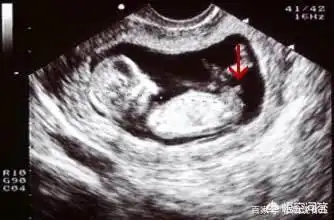

翻12周拍的nt图给大家看看男女.

怀孕十二周可以从b超中的小肿块分辨男女,这真的可以看出来吗?

胎儿从卵泡到性别形成17张图片清晰诠释男宝女宝看得很清楚